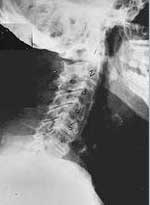

Phase Three Subluxation Degeneration is caused by subluxations that have been continuing on for between 40 and 65 years. This phase has all of the attributes of the previous phases, only worse. The curvatures are abnormal, the disc spaces are vastly decreased and changed. Calcium changes on the spine are abundant in this phase. Normally, people in phase three have a restricted range of motion and probably exhibit symptoms of some kind. In phase three the vertebrae show obvious changes and mutations in shape. Projections made of calcium, sometimes referred to as "spurs or lipping", can be readily seen on x-ray. Chiropractic reconstructive care for patients in phase three ranges from 2.5 years to 3.5 years. This does not mean that at the end of this time that any or all of the calcium changes will be gone. In many instances the body adapts to the presence of the calcium and positive changes can only be measured from a functional standpoint. As before, if Phase Three Subluxation Degeneration is left unchecked it slowly advances onward into the next phase.

Phase four subluxation degeneration is seen with subluxations that have been raging on uncorrected or altered for over sixty five years. Phase four is a grave condition that will negatively affect the patients longevity and quality of life. The massive amount of neurological damage caused by years of subluxation that have lead to phase four are probably taking a serious toll on this person's health status. X-rays in phase four show serious severe structural changes. Vertebrae exhibit massive calcium changes, disc spaces appear blurred, and the bones themselves appear fused. In this scenario the patient will have a severe restriction of range of motion in addition to probably a number of other health issues. Reconstruction may not be possible in phase four, but care can be directed to some reduction in subluxation with the goal of improvement in the quality of life remaining. Patients in Phase Four Subluxation Degeneration have a serious situation both structurally and neurologically, but they are certainly not beyond hope. Many patients in phase four report significant improvements in symptoms, conditions, mobility and quality of life.